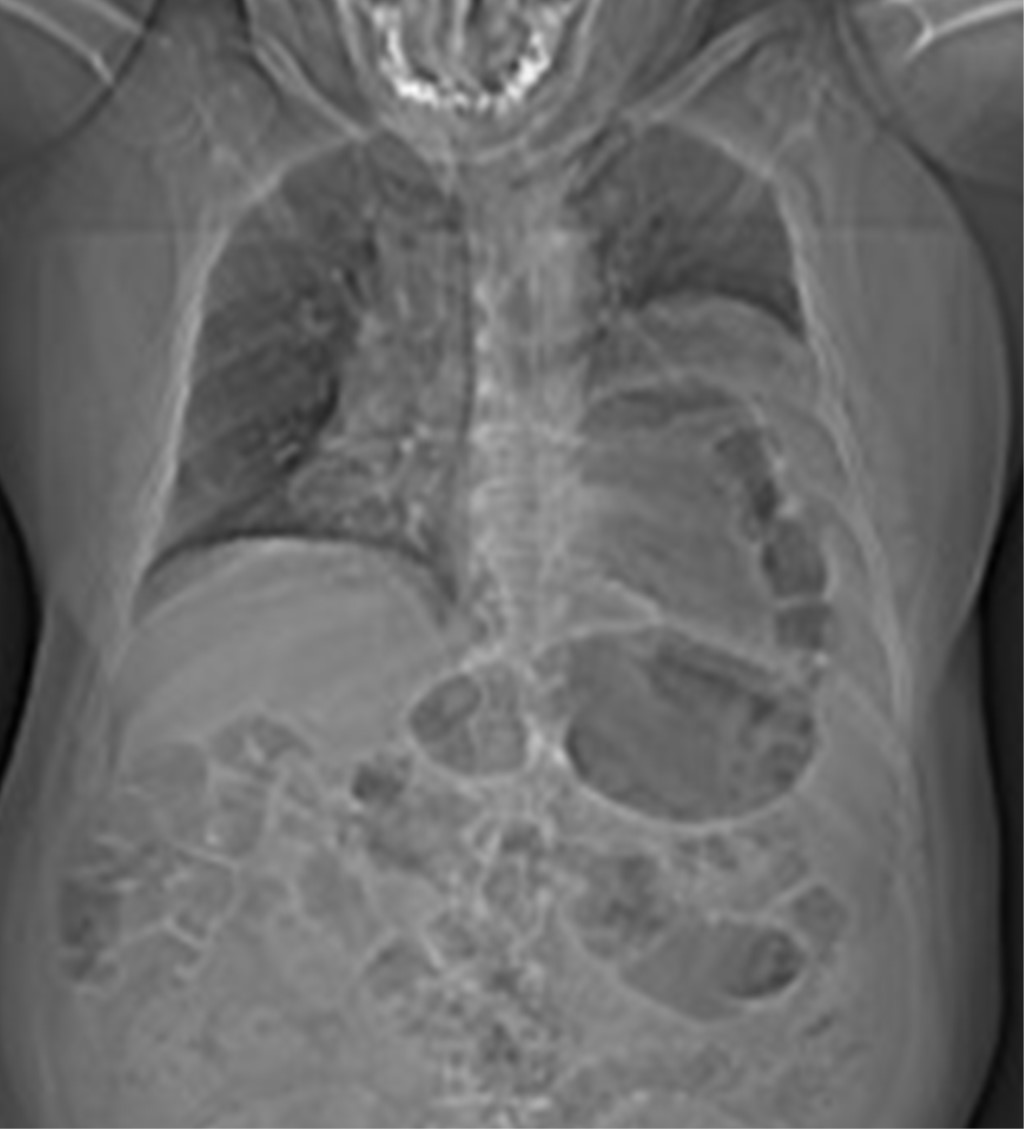

Cursó con distensión abdominal y ausencia de evacuaciones, se realizó radiografía de tórax (Figura 1), la cual mostró disminución del parénquima pulmonar izquierdo por presencia de burbuja aparentemente hidroaérea gástrica; ante estos hallazgos se decidió realizar tomografía de tórax (Figura 2) que reportó nivel hidroaéreo arriba del límite diafragmático izquierdo haciendo un cuello de botella en la continuación del tracto digestivo, además de visualizarse bazo con engrosamiento cicatrizal en la periferia hacia pared torácica.

Figura 1